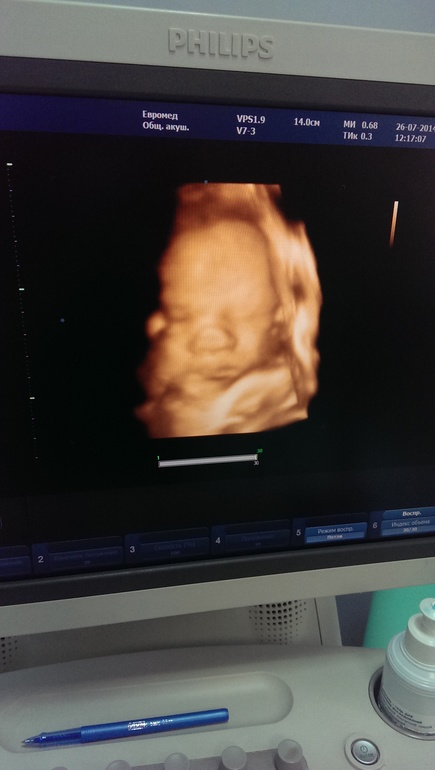

еще хуже вчерашнего!!! Туя я уже рассмеялась! Конечно, из часа измерений 40 минут малыш мой спал и только 20 минут бодрствовал+приехала натощак, чтобы сдать анализы, потом укол фраксипарина в живот ну и капильница! Понятно, что сыночек мой в таких условиях ничего им изображать не хотел. Но Евромед встал на уши. Позвонили моегу врачу, потом главному врачу и решили отправить меня 2 часа погулять и покушать. Так и сделали. Какого было их удивление, когда на следующем измерении за 40 минут малыш утихомирился лишь на 5 минут. Показания - 0,6! Что и требовалось доказать. Зла не хватает! Ну как за 2 часа могут так координально измениться показания? Врач у меня опытный, ну неужели за 20 лет практики он не смог предугадать похожего положения дел? Все нервы перетрепали!!! А на следующий день (то сеть вчера) пришла на контрольный доплер, дабы закрепить и на сколько же было удивление узистки, которая помнила нас еще с прошлого планого доплера по отменным показаниям,, а тут на тебе. Чуть ли не экстренные роды. Все перепроверили- цитирую "лучше результатов и быть не может. Идеальные кровотоки" Хех-еще бы. И фотку сделали.

Ну как у такого лапули там может быть что-то не так? Так что, девочки, верьте в себя и своих малышей, а не в этих врачей и машины, которые когда перестраховываются даже не считают нужным поберечь нервы своих подопечных мамашек. Им повезло еще, что я достаточно хорошо умею контролировать эмоции. Другая бы там такую истерику закатила... Мало бы не показалось. Так что теперь, когда я знаю, что все хорошо-откажусь от этого метода измерения состояния плода.